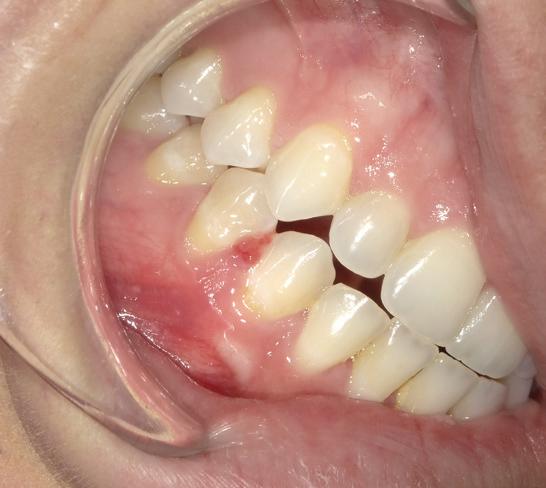

Pathologic jaw lesions associated with impacted teeth

54 Oral Medicine, Oral Diagnosis, Oral Pathology

An unusual clinical and histopathologic presentation of a maxillofacial ameloblastoma: a literature review and case report

Pallavi Parashar

Clayton Davis